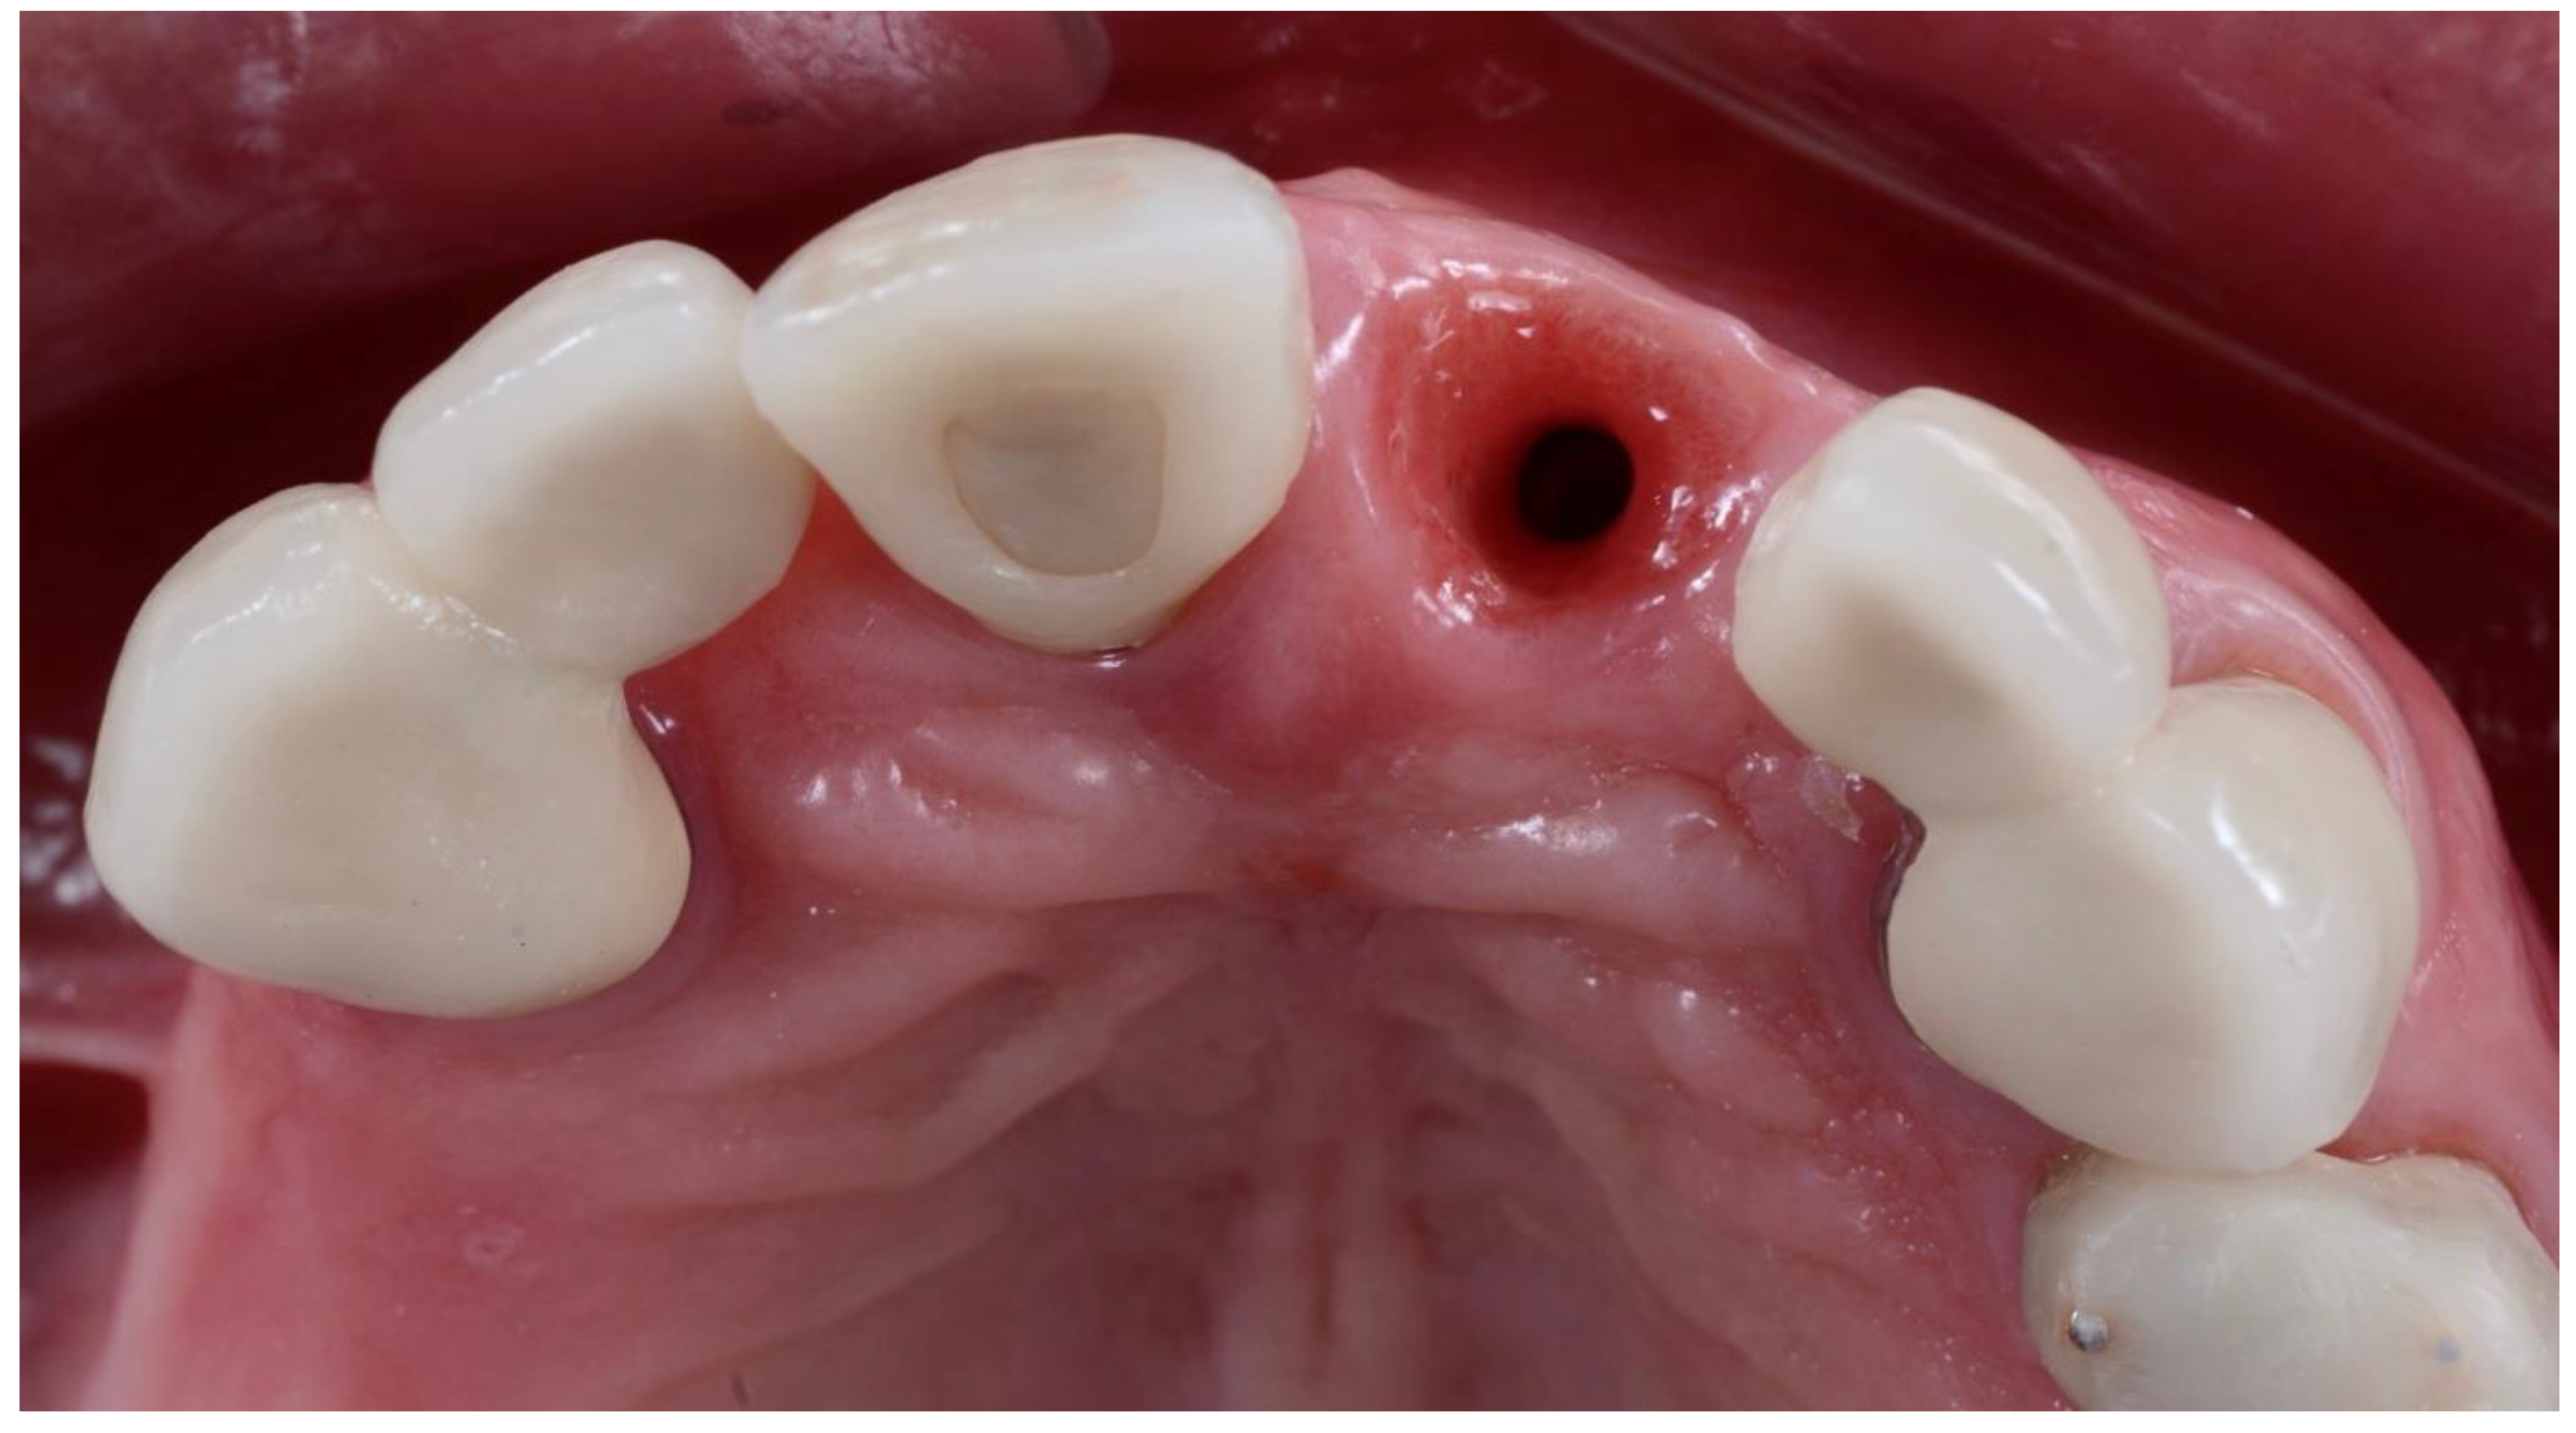

2.1. Surgical Technique